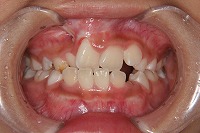

反対咬合を主訴に来院された、右側唇顎裂の10歳6ヵ月の女の子です。診断「右側唇顎口蓋裂で反対咬合を伴う」1期治療で反対咬合の解消と上顎の前歯の並びを修正しました。2期治療は抜歯をせず治療を行いました。